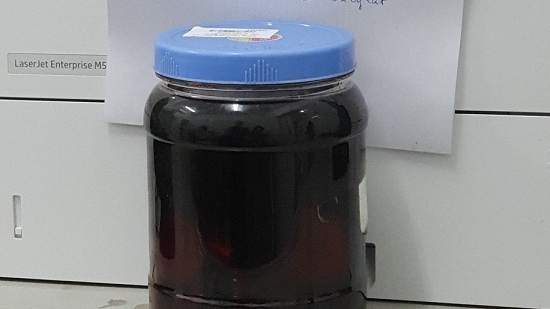

Tổn thương não, hôn mê do uống rượu ngâm rễ cây rừng

Nghe theo lời mách của một "bà dân tộc", ông T.V. Đ (SN 1962, ở Nghệ An) lên rừng đào rễ cây về ngâm rượu uống để chữa bệnh xương khớp. Sau 10 ngày sử dụng, ông Đ, đã phải nhập viện cấp cứu vì tổn thương não.